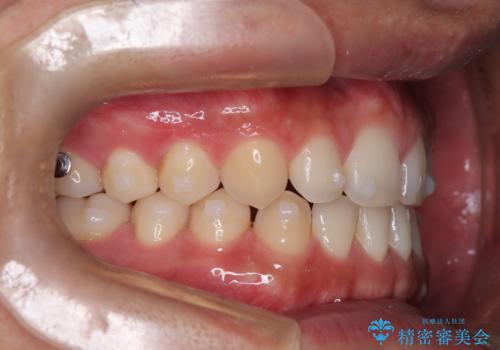

前歯の隙間が気になる マウスピース矯正

- 前歯がすきっ歯であることを気にされて来院された患者様です。上下顎のアーチを整える治療計画を立案し、マウスピースにて治療しました。とてもまじめに使用していただき、気になっていた隙間も順調に閉鎖しました。